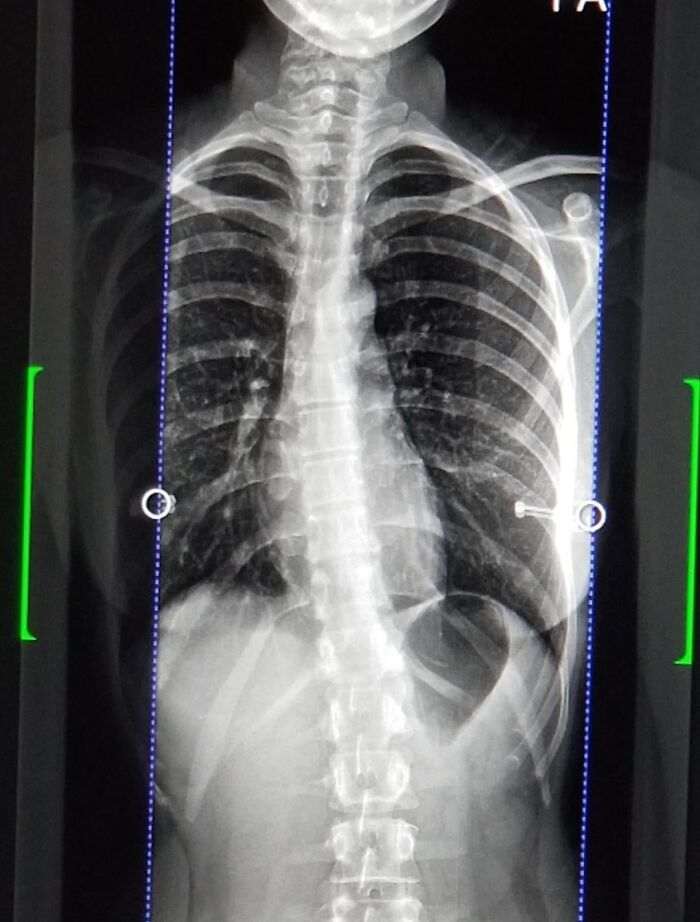

#41 Struggling To Breathe For Years. Doctors Don’t Help Because I’m “Too Young” To Be Having Issues

Image source: medical